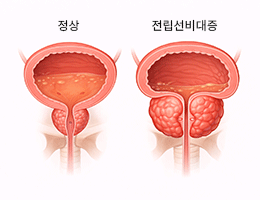

전립선비대증 (Benign Prostatic Hyperplasia (BPH))